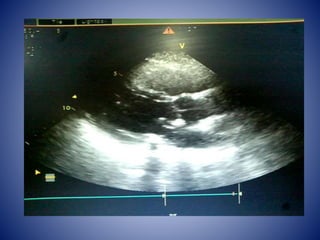

• On 29th Jan Screening Echo was done which

showed IHD , RWMA +, Myxomatous MV,

dIlated LA, moderae MR, Grade 1 AR,

moderate TR, Severe PAH (PASP 62mmHg), EF

50%, no clots /vegetations.